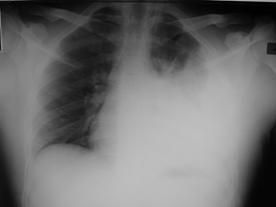

Traumatism toracic deschis Hemotorace stang masiv

Hemotorace stang masiv Hemotorace stang masiv

Hemotorace

drept masiv Hemotorace stang

Imagine CT Radiografie efectuata in ortostatism